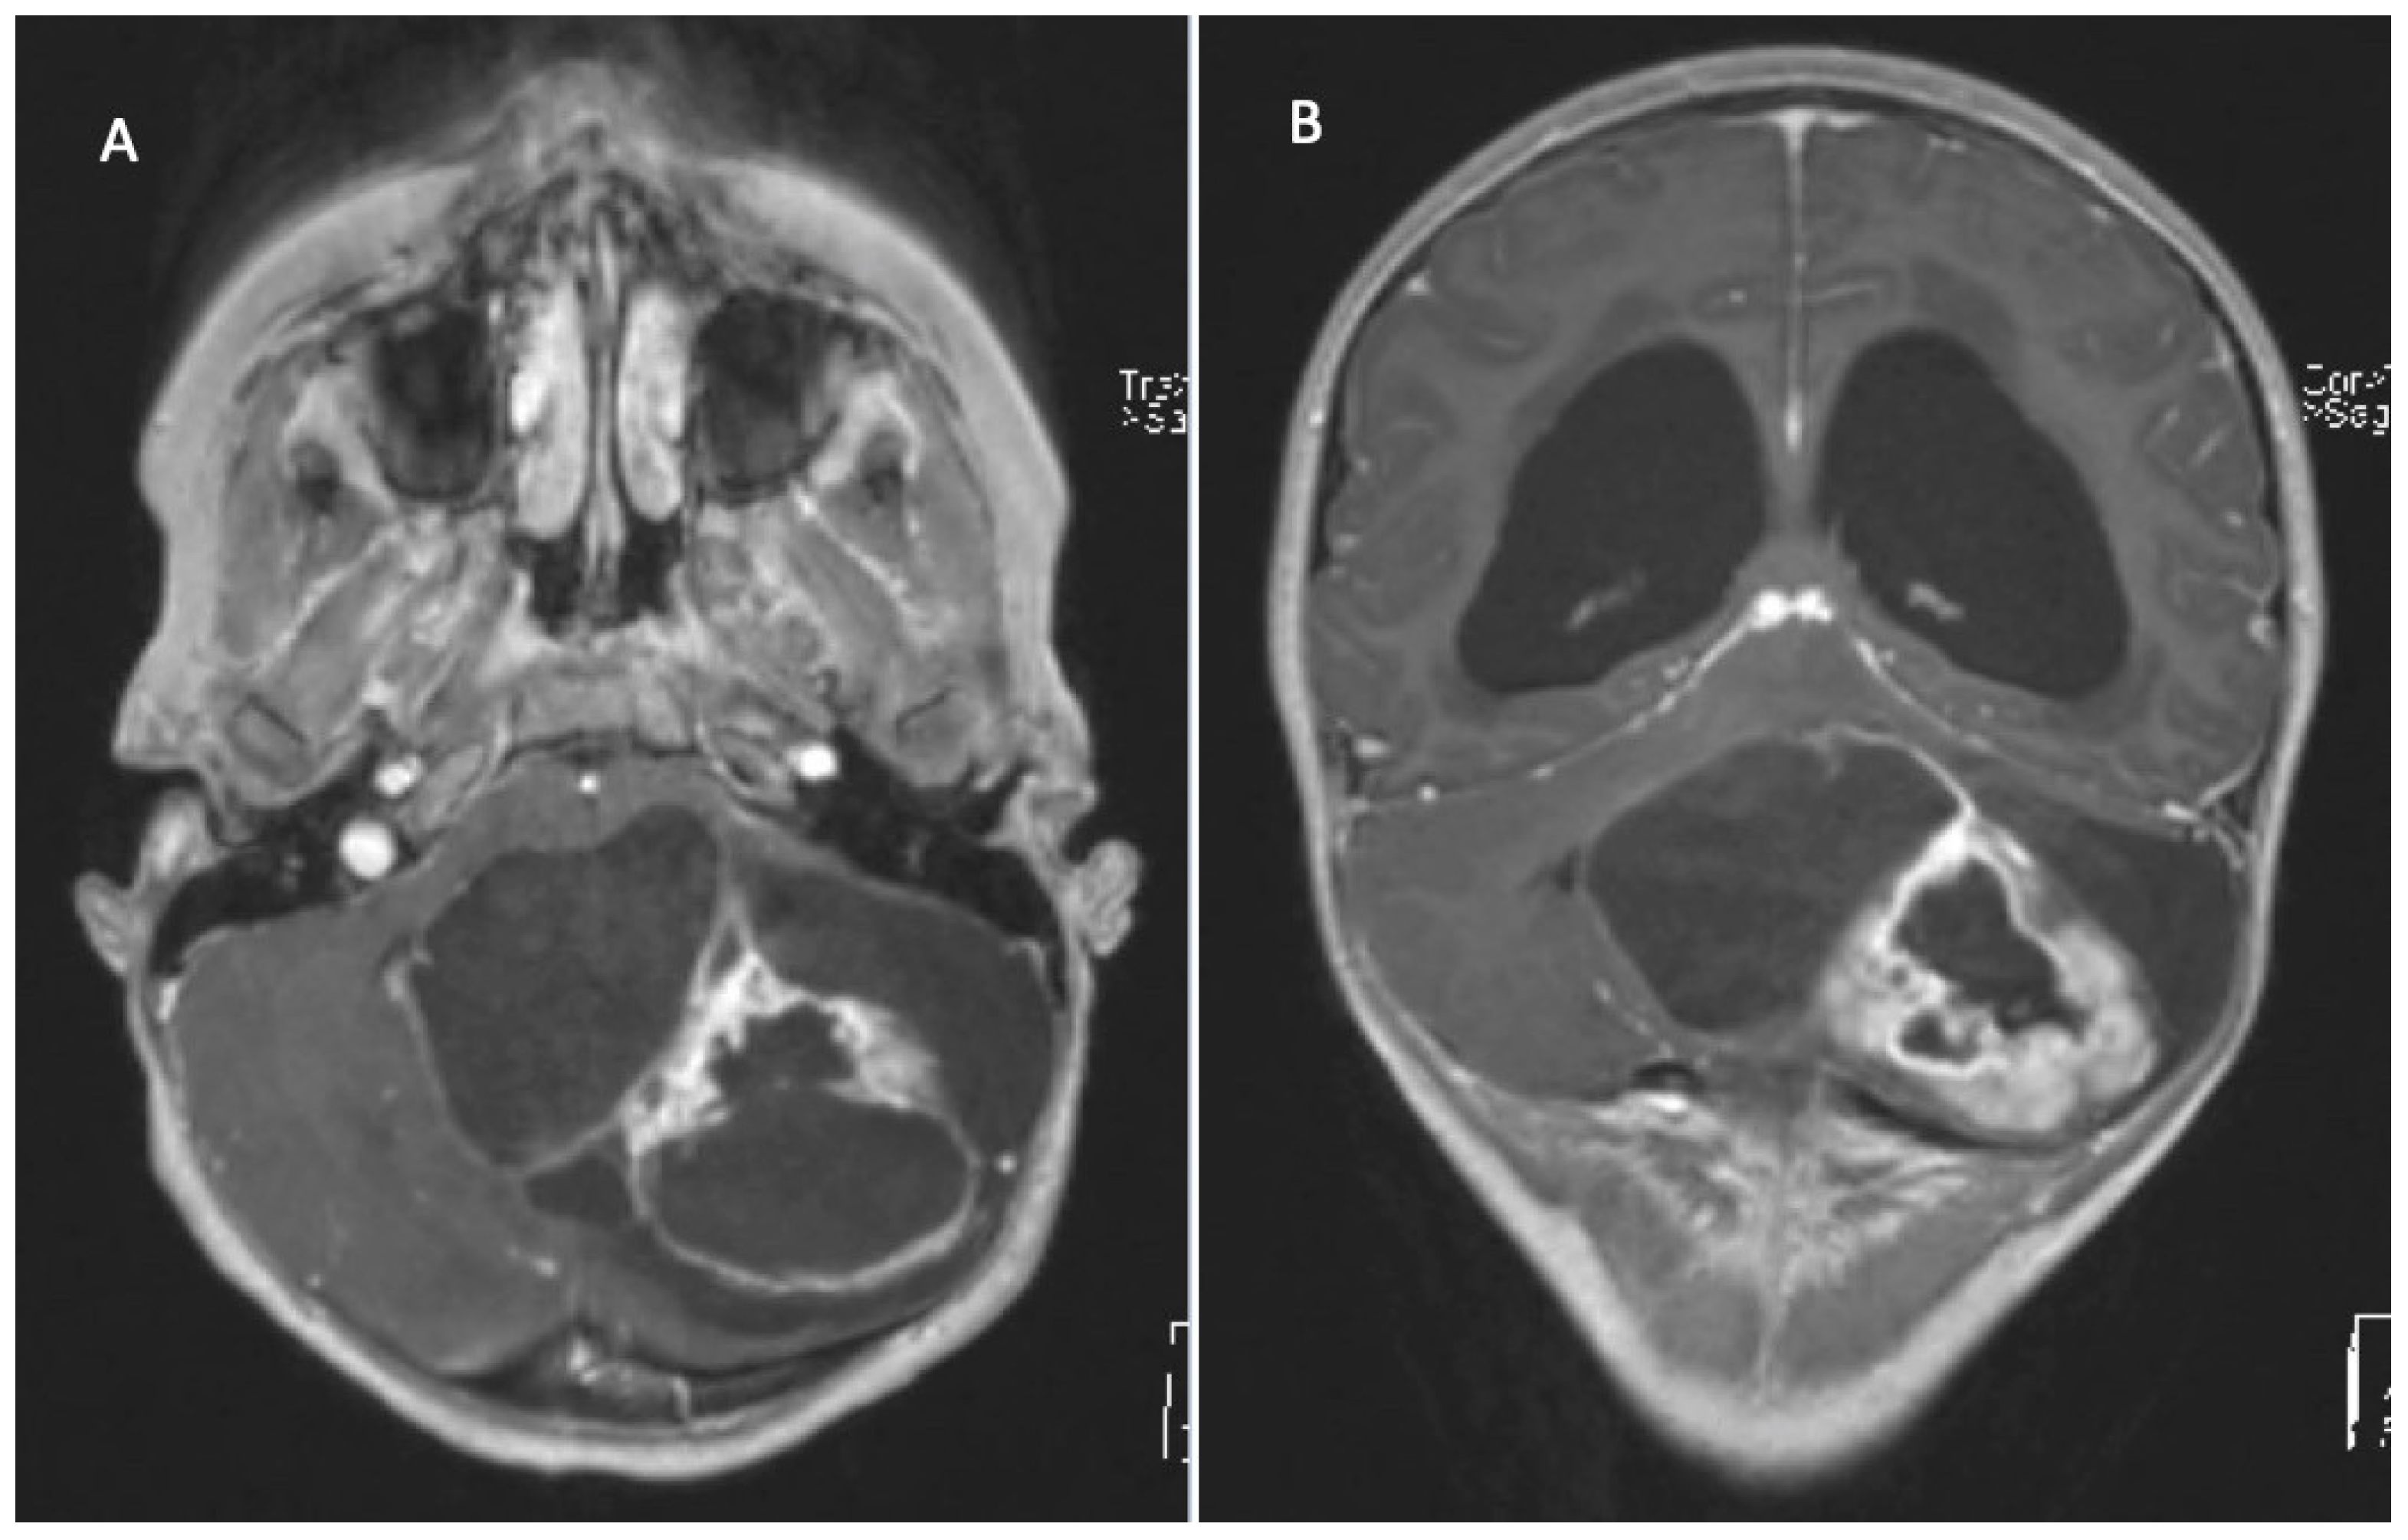

2. Clinical Assessment/Symptoms

3. Diagnostics